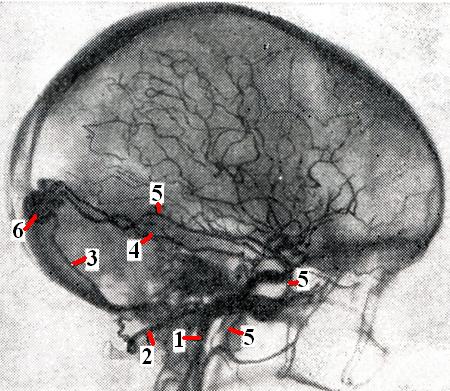

Артерио-синусные соустья образуются между артериями твердой мозговой оболочки и ее венозными синусами (рис. 3): верхним сагиттальным, прямым, поперечным, сигмовидным, каменистыми и кавернозным. Чаще всего соустье развивается при прорыве задней менингеальной ветви в сигмовидный или поперечный синус (окципито-синусное соустье). В связи с большой разницей давления в артерии и вене возникшее соустье способствует мощному развитию приводящих артерий в твердой мозговой оболочке и покровах черепа. Затылочная артерия может достигать 4—5 мм в диаметре и полностью опорожняется в синус. Сюда же может направляться кровоток из средней менингеальной, возвратной глазничной артерий, ветвей кавернозного отдела внутренней сонной и корковых ветвей средней мозговой артерии.

Диагноз: при сдавлении пальцами сонной и затылочной артерии и пульсирующих мягких тканей прекращается или резко ослабляется сосудистый шум, который прослушивается позади ушной раковины. На рентгенограмме иногда выявляется узура кости у сосцевидного отростка. С помощью ангиографии определяют локализацию соустья и источники его кровоснабжения; необходимо раздельно исследовать бассейны внутренней, наружной сонных и позвоночной артерий на стороне соустья.

Лечение хирургическое, состоит в последовательном (в несколько этапов) выключении приводящих сосудов путем: 1) резекции затылочной артерии у сосцевидного отростка; 2) широкого скальпирования черепа в области сосцевидного отростка и тампонады сосцевидного канала мышцей; 3) внутричерепного выключения артерий, несущих кровь к соустью.

Перевязка только наружной сонной артерии малоэффективна. В случае соустья между твердооболочечными артериями и кавернозным синусом, симулирующего каротидно-кавернозное соустье, необходима эмболизация мелкими мышечными фрагментами средней менингеальной и верхнечелюстной артерий, так как они являются основными источниками кровоснабжения соустья.